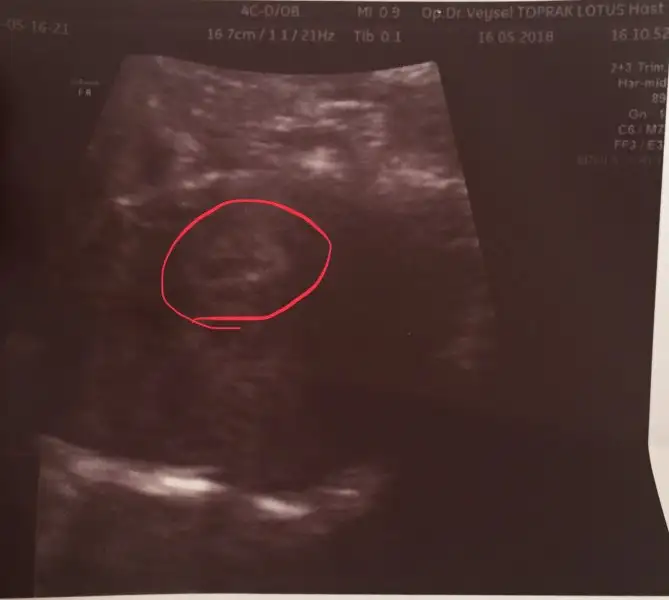

Kızlar kesemiz bu kırmızı halkanın içinde. Karından baktı vajinadan bakmadı. Çok şükür gördük. 25Mayıs’a da çağırdı kalp atışı için. Allah herkese nasip etsin inşşşşş. Çok güzel bi duygu. Ağladım valla eşim çok heyecanlandı mutlu oldu.

Eki Görüntüle 2147020 Kızlar kesemiz bu kırmızı halkanın içinde. Karından baktı vajinadan bakmadı. Çok şükür gördük. 25Mayıs’a da çağırdı kalp atışı için. Allah herkese nasip etsin inşşşşş. Çok güzel bi duygu. Ağladım valla eşim çok heyecanlandı mutlu oldu.